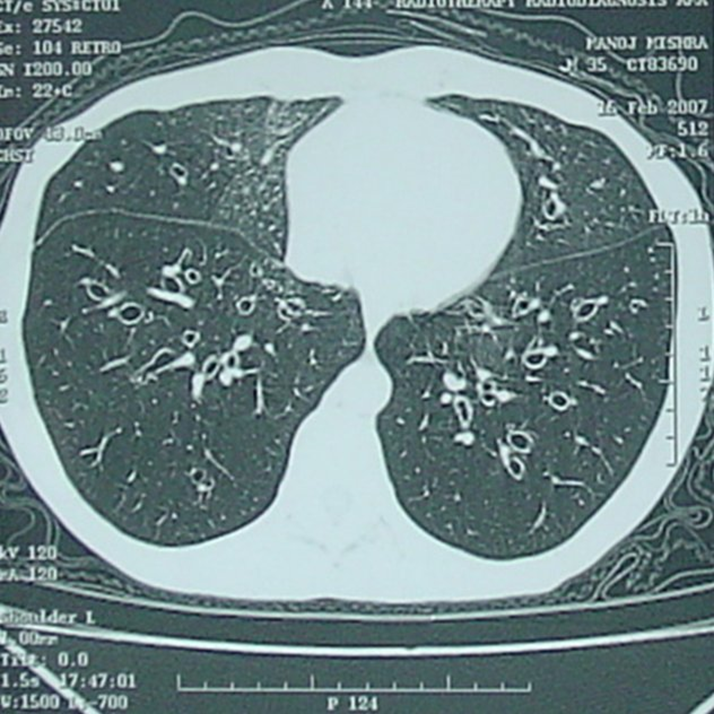

- КТ высокого разрешения: является «золотым стандартом» в структуре диагностики бронхоэктатической болезни. Дилатация бронхов >1,5 раз в ширину как рядом расположенный сосуд, бронхиальная стенка истончена, отсутствие нормальных сужений, наличие кист (см. рис. 2).

Рис.2